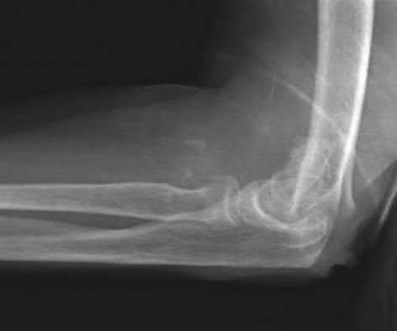

Figures A and B show a distal humerus fracture without traction (A) and with traction (B) applied. Illustration A shows the same fracture after bicolumnar plating. Illustration B shows the different surgical approaches to the distal humerus (A, Campbell triceps splitting; B, O'Driscoll triceps reflecting anconeus pedicle [TRAP]; C, Bryan-Morrey triceps reflecting; D, olecranon osteotomy)